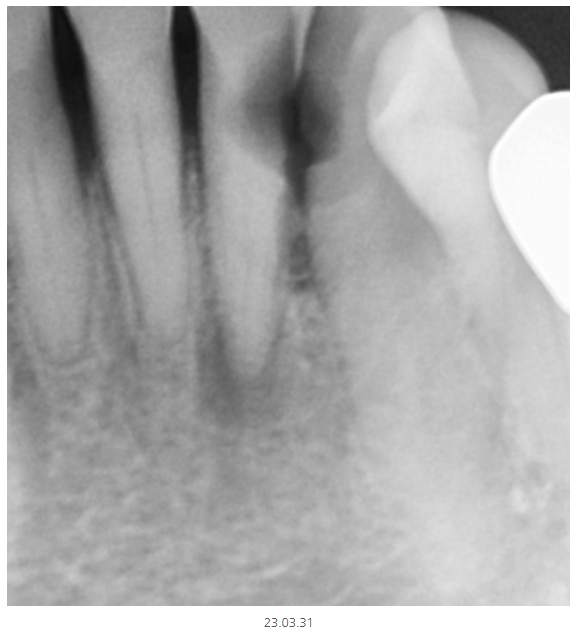

파노라마에서 1차 판별해 보니

의심되는 부분이 있다!!

그러면 추가 검사가 들어가게 됩니다.

이럴 때 선택적으로 작은 x-ray를 촬영합니다.

부분적으로 확대하여 촬영하기 때문에

더 자세히 볼 수 있습니다.

정상적인 치아는 하얗게 속이 보이지만

충치가 파먹은 부분은

까맣게 나타나거든요~

텅~ 속이 비어있기 때문이죠.